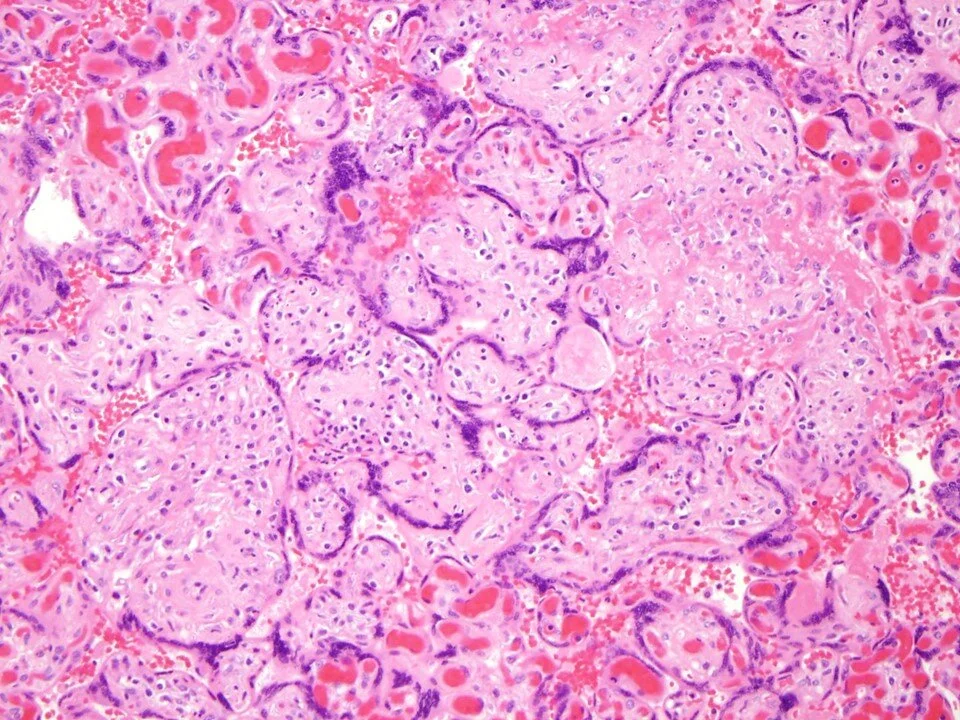

Acute subchorionitis

Acute chorionitis - neutrophils within cellular chorion

Acute chorioamnionitis: neutrophils extend into fibrous chorion